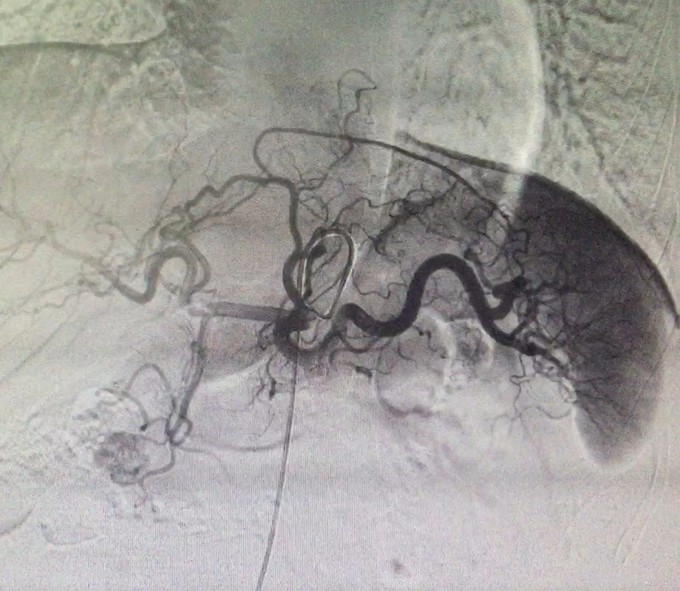

查体:神清,腹软,未及包块,无压痛及反跳痛,神经系统检查未见异常 辅查:外院头颅CT平扫:腔隙性脑梗;胰腺CT平扫:胰头、十二指肠降部稍低密度影,肝内多发小囊肿;上腹部增强CT:胰腺低密度影,考虑良性;肝内多发小囊肿。 入院检查:血、尿、粪常规、肝肾功能、电解质、凝血功能正常;AFP、CEA、CA19-9、CA125、CA15-3、CA72-4均正常;胰岛素78.33mIU/L,C肽 4.91ug/L。腹腔动脉DSA:胰头区富血供肿瘤; 胰腺增强MRI:1、胰头部富血供病变,考虑胰岛素瘤可能性大;2、肝内多发小囊肿。